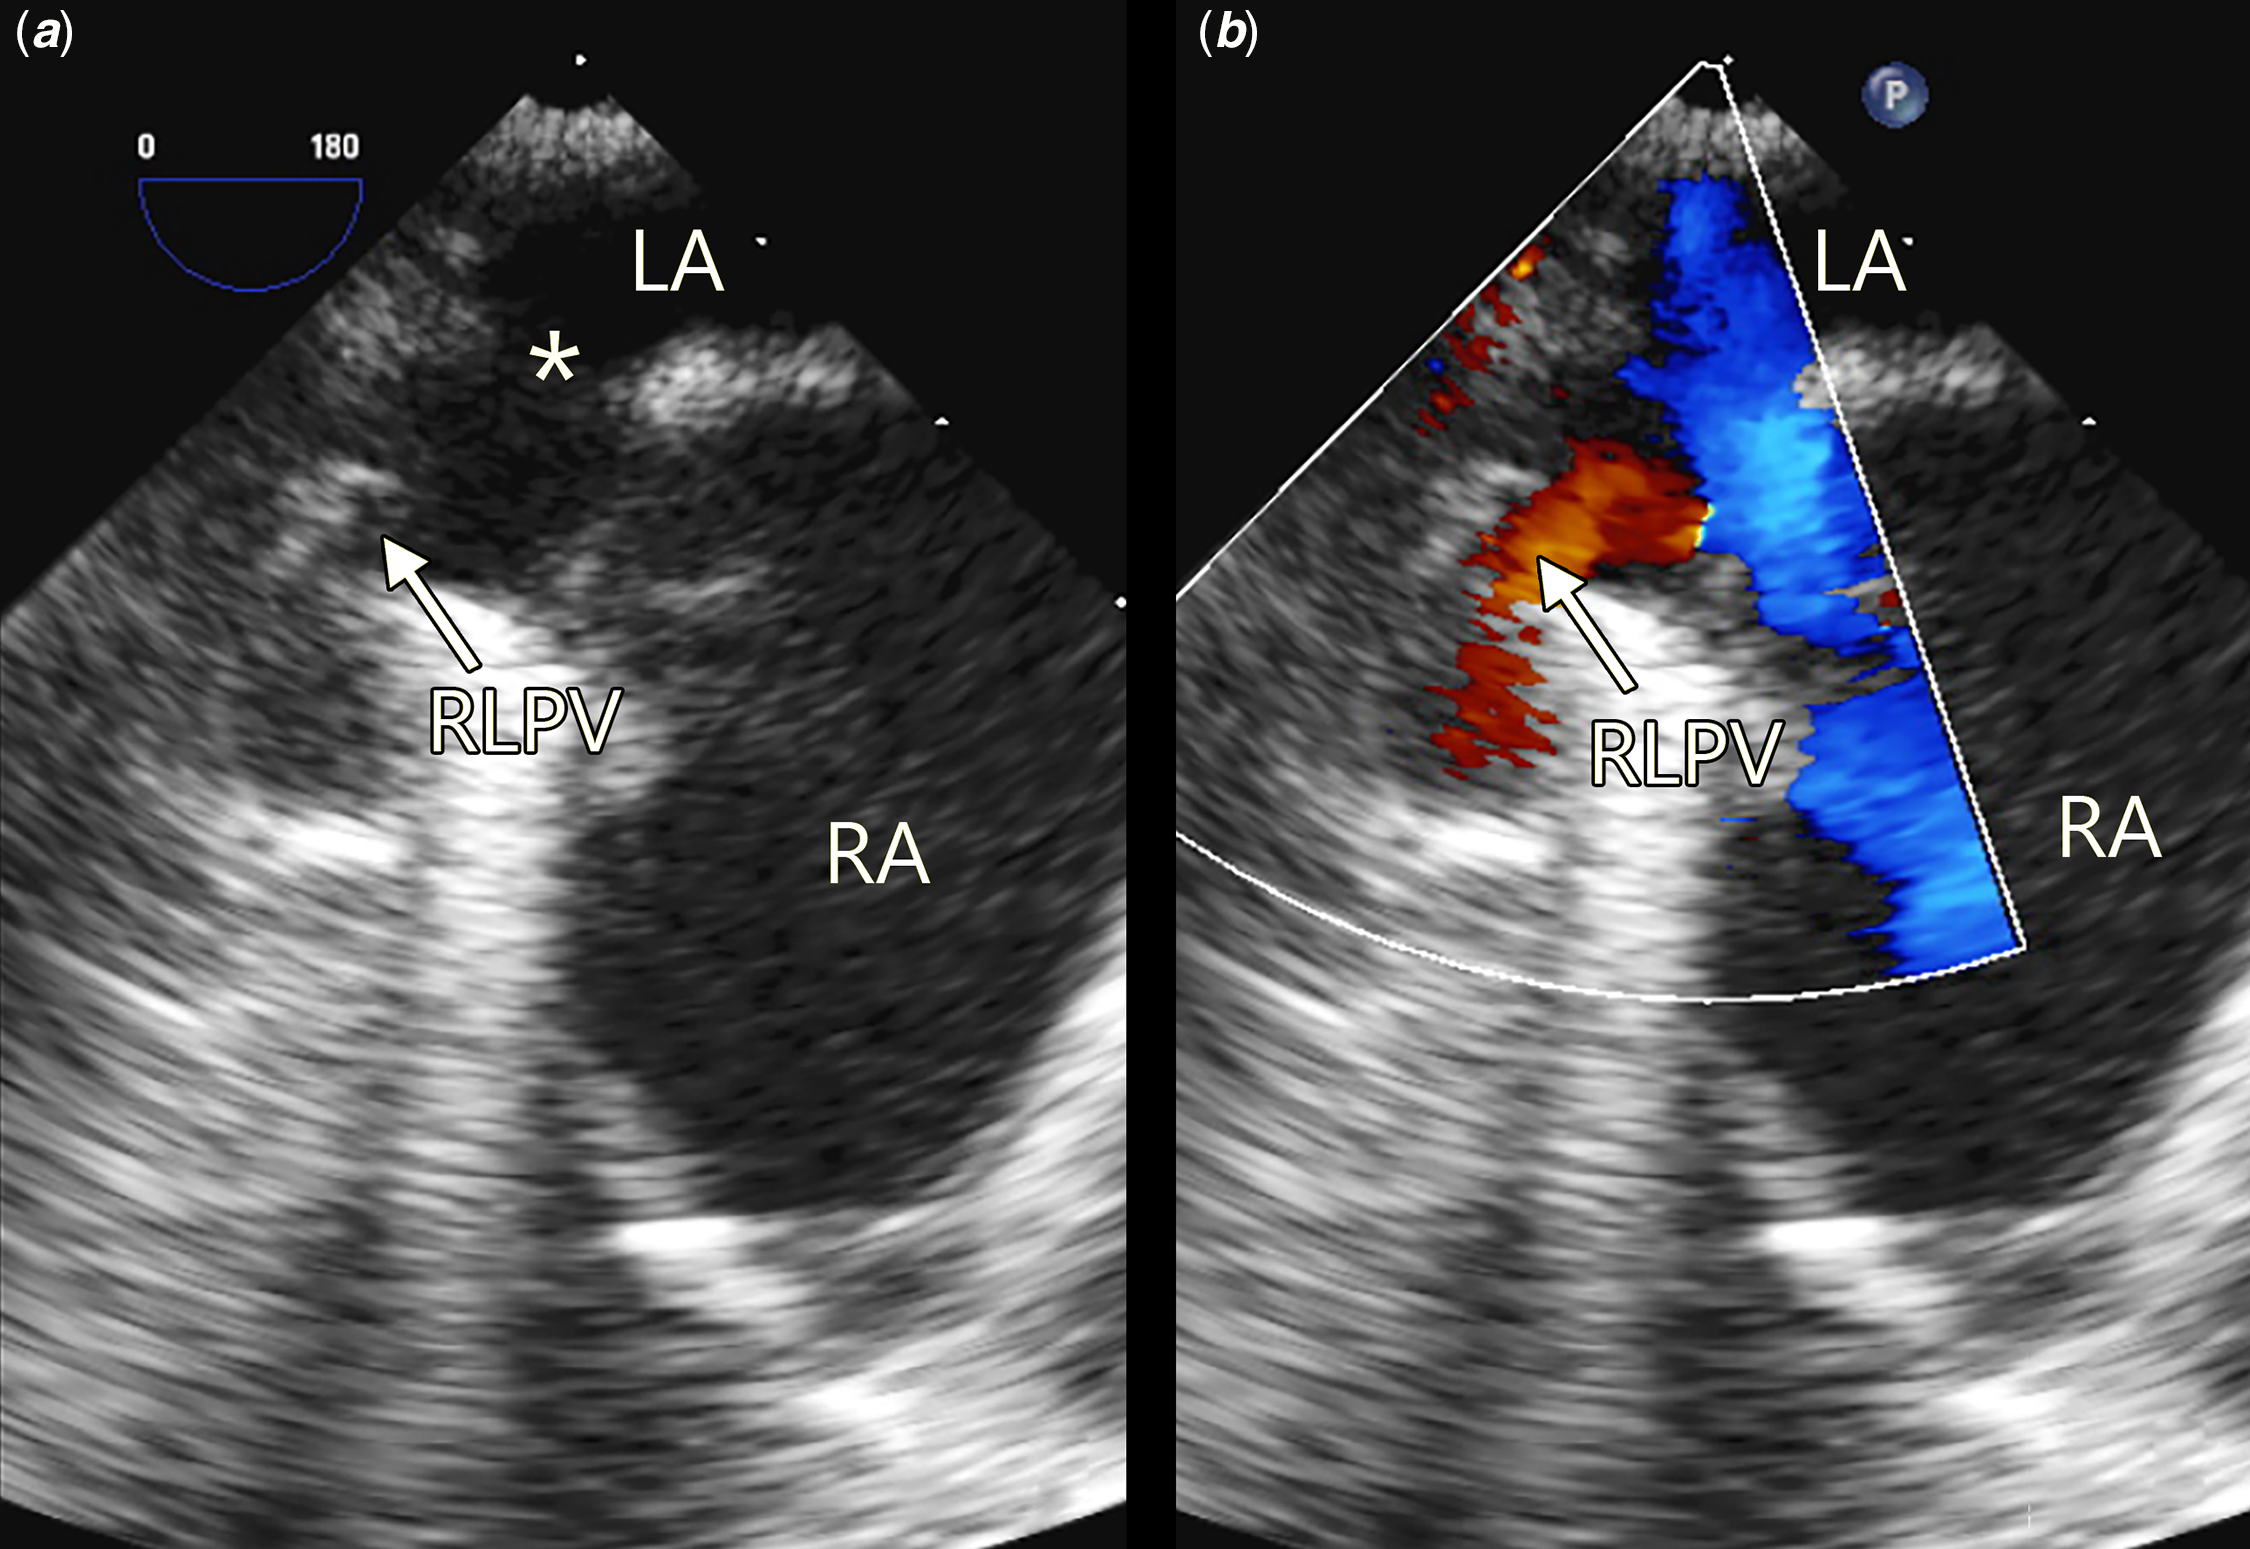

The median age at diagnosis was 4.2 years (range 0.5−15.5 years of age). In 32 of 37 (86%) patients, sinus venosus defect was diagnosed and partial anomalous pulmonary venous drainage were suspected or diagnosed by two-dimensional transthoracic echocardiogram including a subcostal sagittal-oblique bicaval view scanning from the sinus venosus defect to the anomalous pulmonary venous connection (Fig 1). In 5 of the 37 patients, the sinus venosus defect could not be visualised on transthoracic echocardiogram alone. In three of these five patients, who presented with unexplained right ventricular volume overload, the final diagnosis was achieved by transoesophageal echocardiogram (Fig 2); one of these three patients underwent further diagnostic cardiac catheterisation and cardiac CT. In two of these five patients, the diagnosis of sinus venosus defect and partial anomalous pulmonary venous drainage was reached intra-operatively. One of these two patients has an additional diagnosis of complex ventricular septal defect and the other was diagnosed with an inferior sinus venosus defect.

Figure 2. ( a and b ) Transoesophageal echocardiogram demonstrating the sinus venosus defect (*) and the anomalous right lower pulmonary vein (RLPV) draining directly into the right atrium (RA). LA=left atrium.